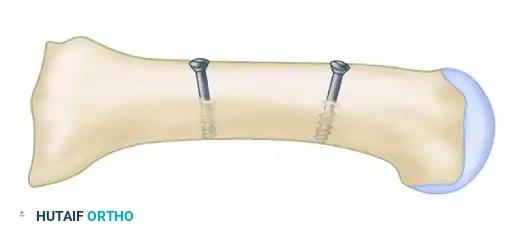

Phase 4: Reduction and Internal Fixation

Achieving and holding the correct multiplanar reduction is the most technically demanding portion of the procedure.

- Mobilization: Insert a Freer elevator into the osteotomy site to verify that no periosteal hinges remain medially or laterally. The fragment must be completely mobile.

- Displacement and Rotation:

- Displace the proximal fragment medially and hold it securely with a Freer elevator.

- Simultaneously, rotate the distal fragment laterally around the osteotomy site (typically requiring 2 to 4 mm of lateral translation/rotation).

- Pitfall Avoidance: Strictly prevent the distal fragment from sliding dorsally (which causes transfer metatarsalgia) or plantarward.

- Fixation: While the surgeon holds the exact reduction, an assistant completes the fixation.

- Place a centering device ("golf tee" or "mushroom" guide) into the pre-drilled 3.5-mm glide hole.

- Drill the proximal fragment with a 2.0-mm or 2.5-mm drill bit.

- Tap the proximal fragment with a 4.0-mm tap.

- Insert a 4.0-mm fully threaded cancellous screw (typically 26 mm in length).